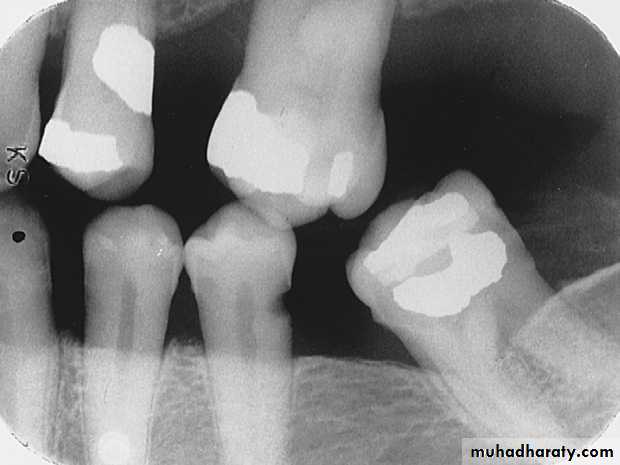

Rampant CariesRampant caries is advanced and severe caries that affects numerous teeth

Rampant caries is typically seen in children with poor dietary habits or in adults with decreased salivary flow.